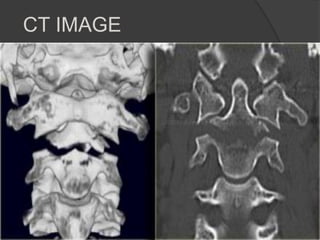

CT IMAGE

The image through the lateral part of C2 nicely shows, that the fracture runs

through the body of C2, i.e. a type III odontoid fracture.

The posterior dura is in a normal position, but the anterior dura is displaced

(arrow).

Showing Central location of spinal cord injury